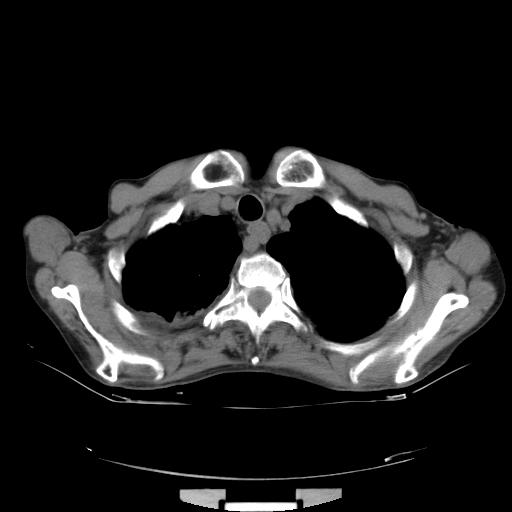

女,72岁,咳嗽一周余,突发右下肢无力二天。

pe:bp-140、80mmhg,精神可,伸舌居中,右上肢肌力正常,右下肢肌力0级,巴氏征+

来院做头颅+胸部ct平扫

前两张头颅片子是平扫,请问能否考虑机化性肺炎或者间皮瘤?

本例颅内见多发大小不等高密度灶,有强化及水肿;另外,胸锁关节层面可能是第四胸椎及右侧肋骨起始部骨质欠连续,椎旁软组织肿胀,建议调骨窗观察。

右侧胸膜间皮瘤,双肺大泡,颅内多发转移(右顶叶、左侧侧脑室前角放射冠区)并出血。

左侧额叶及右顶叶实质内病灶首先应该考虑是转移性肿瘤伴出血{结合胸部强化}.